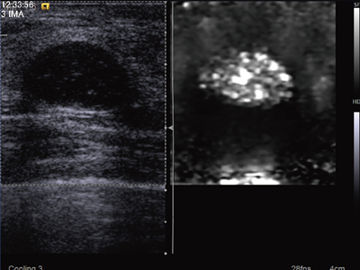

■手で押さないエラストグラフィ ─ Virtual Touch Tissue Imaging

組織の硬さを画像表示するエラストグラフィが,乳腺領域を中心に使われるようになってきた。これは,超音波プローブを軽く押し付けて組織を変形させ,その程度を画像化する手法である。しかし,手動で圧迫する従来の手法では,組織内部の応力の偏りが生じやすく,操作者依存性を内在している。そこで,手で押す代わりに音の放射力を利用する“Virtual Touch Tissue Imaging”を開発した。プローブは体表に固定したままで撮像可能なため,安定したエラストグラフィが得られる(図1)。